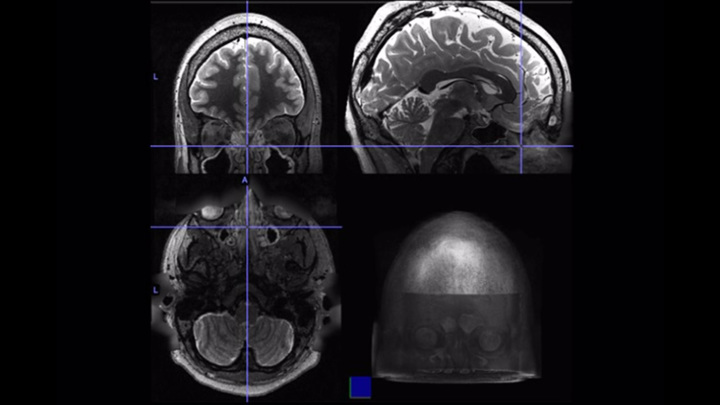

연구 참가자 중 한 명의 뇌의 기능적 MRI 스캔.

사진 : Dr. Aria Jafari / University of Washington School

이 사람들 의 기능적 MRI를 비교 한 결과 과학자들은 한 번에 몇 가지 중요한 결론에 도달했습니다.

MRI는 뇌의 혈류 변화를 측정하여 다른 영역에서 뉴런의 활동에 대해 말할 수 있음을 상기하십시오.

혈류가 더 많은 곳에서는 가장 큰 뇌 활동이 기록됩니다.